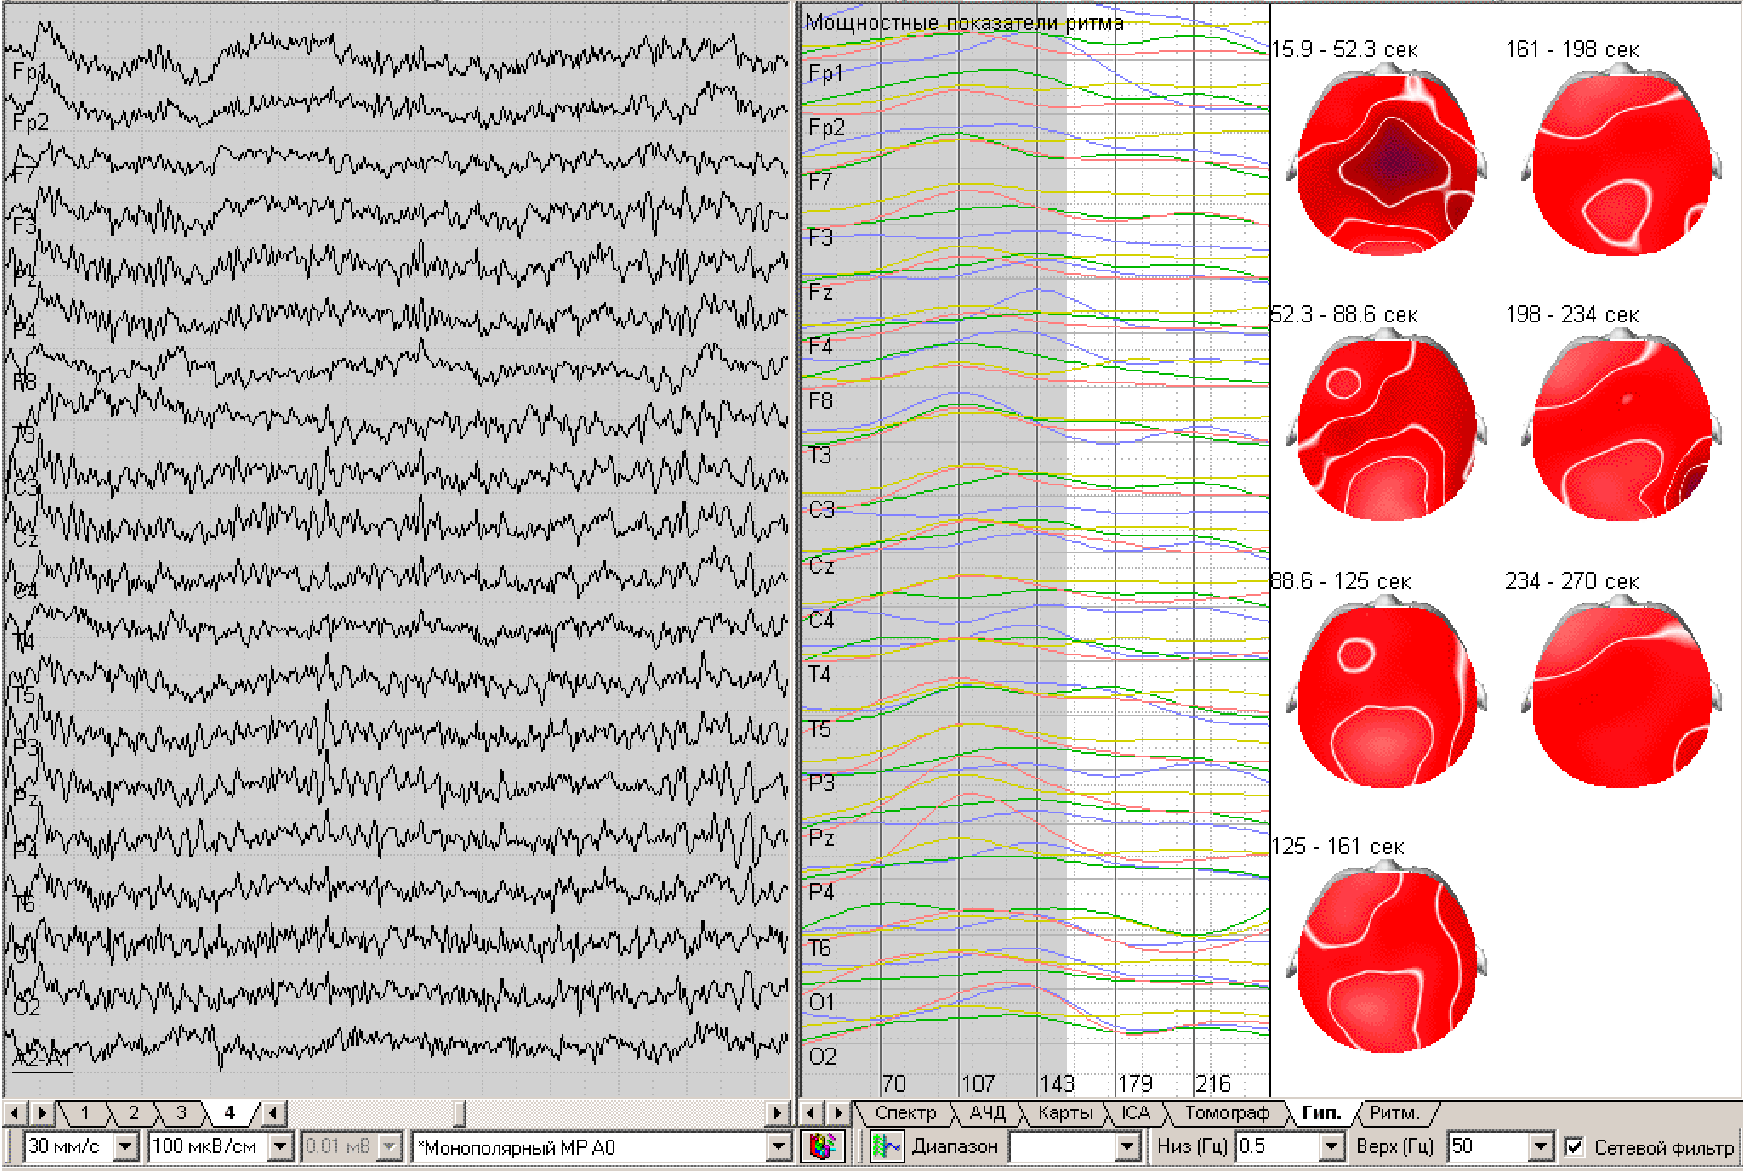

Our client is one of the leading medical technology companies in Ukraine, specializing in functional diagnostic systems. Their product line includes Electroencephalography (EEG), Electrocardiography (ECG), Fetal and Holter ECG monitoring, Rheography (REG/ICG), and Spirometry (SPR) systems — all designed to provide precise, data-driven insights for clinicians. Their products combine multi-channel biosignal acquisition, advanced signal processing, and automated report generation.

The company sought to develop a suite of desktop applications — including NeuroCom (EEG), ReoCom (REG/ICG), and SpiroCom (SPR) — that could deliver deep signal analysis and maximum computational efficiency on standard Windows-based computers, even on older or low-spec machines.

ICA, 3D tomography, artifact removal